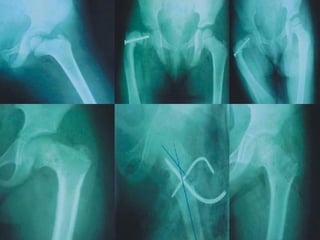

Diagnostico de coxa vara El diagnóstico es fundamentalmente radiológico.  Los signos clínicos incluyen que, El paciente puede tener un corto limite de la marcha, o en casos graves una marcha de Trendelenburg (debido a la restricción de secuestro). Quizá el signo de Trendelenburg positivo.

Tratamiento para Coxa Vara El consenso general para el tratamiento sintomático o progresiva congénita Coxa Vara es con cirugía.  La cirugía permite la reconstrucción del cuello eje angular para lograr una más normal y equilibrada estructura.  Algunos recomiendan que en los casos en que la cirugía es necesaria, que se realice , mientras que el niño es aún menor de edad y no como muchos creen que hay una mayor oportunidad para la articulación de la cadera a remodelar por completo con la nueva estructura de conjunto.

Terapia Conservadora: la desviación prácticamente no puede resolverse mediante métodos conservadores. b) Quirúrgica : - osteotomía correctora intertrocanterea valgizante, - si también existe una reducción de la torsión anterior, se lleva a cabo osteotomía rotativa y valgizante.

Diagnostico de coxavara El diagnóstico es fundamentalmente radiológico. Los signos clínicos incluyen que, El paciente puede tener un corto limite de la marcha, o en casos graves una marcha de Trendelenburg (debido a la restricción de secuestro). Quizá el signo de Trendelenburg positivo.

Tratamiento para CoxaVara El consenso general para el tratamiento sintomático o progresiva congénita Coxa Vara es con cirugía. La cirugía permite la reconstrucción del cuello eje angular para lograr una más normal y equilibrada estructura. Algunos recomiendan que en los casos en que la cirugía es necesaria, que se realice , mientras que el niño es aún menor de edad y no como muchos creen que hay una mayor oportunidad para la articulación de la cadera a remodelar por completo con la nueva estructura de conjunto.

Terapia Conservadora: ladesviación prácticamente no puede resolverse mediante métodos conservadores. b) Quirúrgica : - osteotomía correctora intertrocanterea valgizante, - si también existe una reducción de la torsión anterior, se lleva a cabo osteotomía rotativa y valgizante.